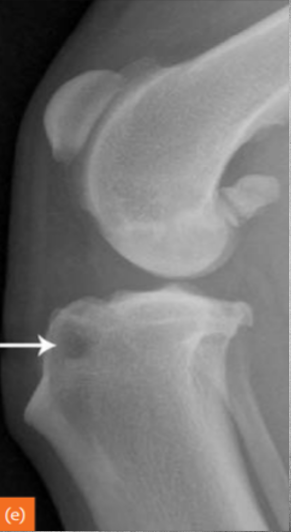

identify

UAP Ununited anconeal process a condition in which a bony protuberance within the elbow becomes detached from the ulna. This loose, bony fragment causes pain and lameness and contributes to articular damage within the elbow joint.